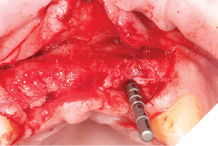

A Papilla sparing extended H-shaped crestal incision was made, full thickness mucoperiosteal flap with clean reflection of the periosteum. The healing alveolar sockets were exposed and used to guide our planned dental implant placements. An initial periosteal release was carried out to allow passive tension free closure (Figs. 10-12).

Fig. 10

Fig. 11

Fig. 12